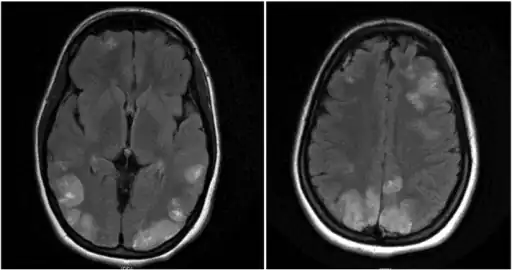

Image shows faint multifocal and bilateral hyperintensities in the frontal lobes and parietooccipital lobes, extending to the left greater than right posterior temporal regions